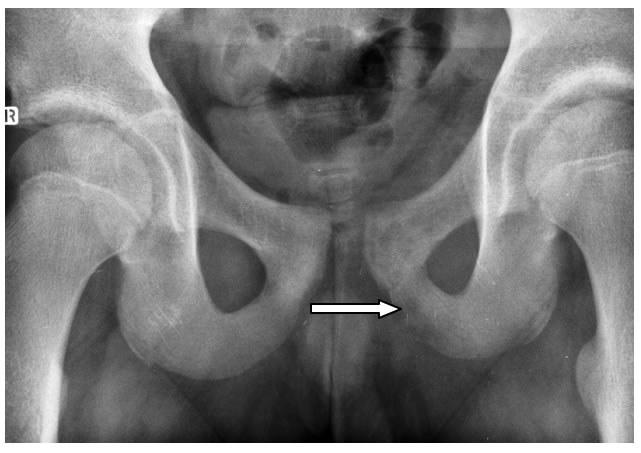

di sx. Alla luce di tali evidenze ripetiamo, poi, una radiografia del

bacino (a distanza di circa 2 settimane dall'esordio della

sintomatologia) che effettivamente dimostra il rimaneggiamento

osteo-strutturale della branca ischio-pubica di sx. confermando,

pertanto, il limite “temporale” di tale metodica. (Figura

2)

Figura

2.

Rx bacino: rimaneggiamento osteo-strutturale della branca

ischio-pubica di sx. ed in misura minore della branca ileo-pubica

omolaterale.